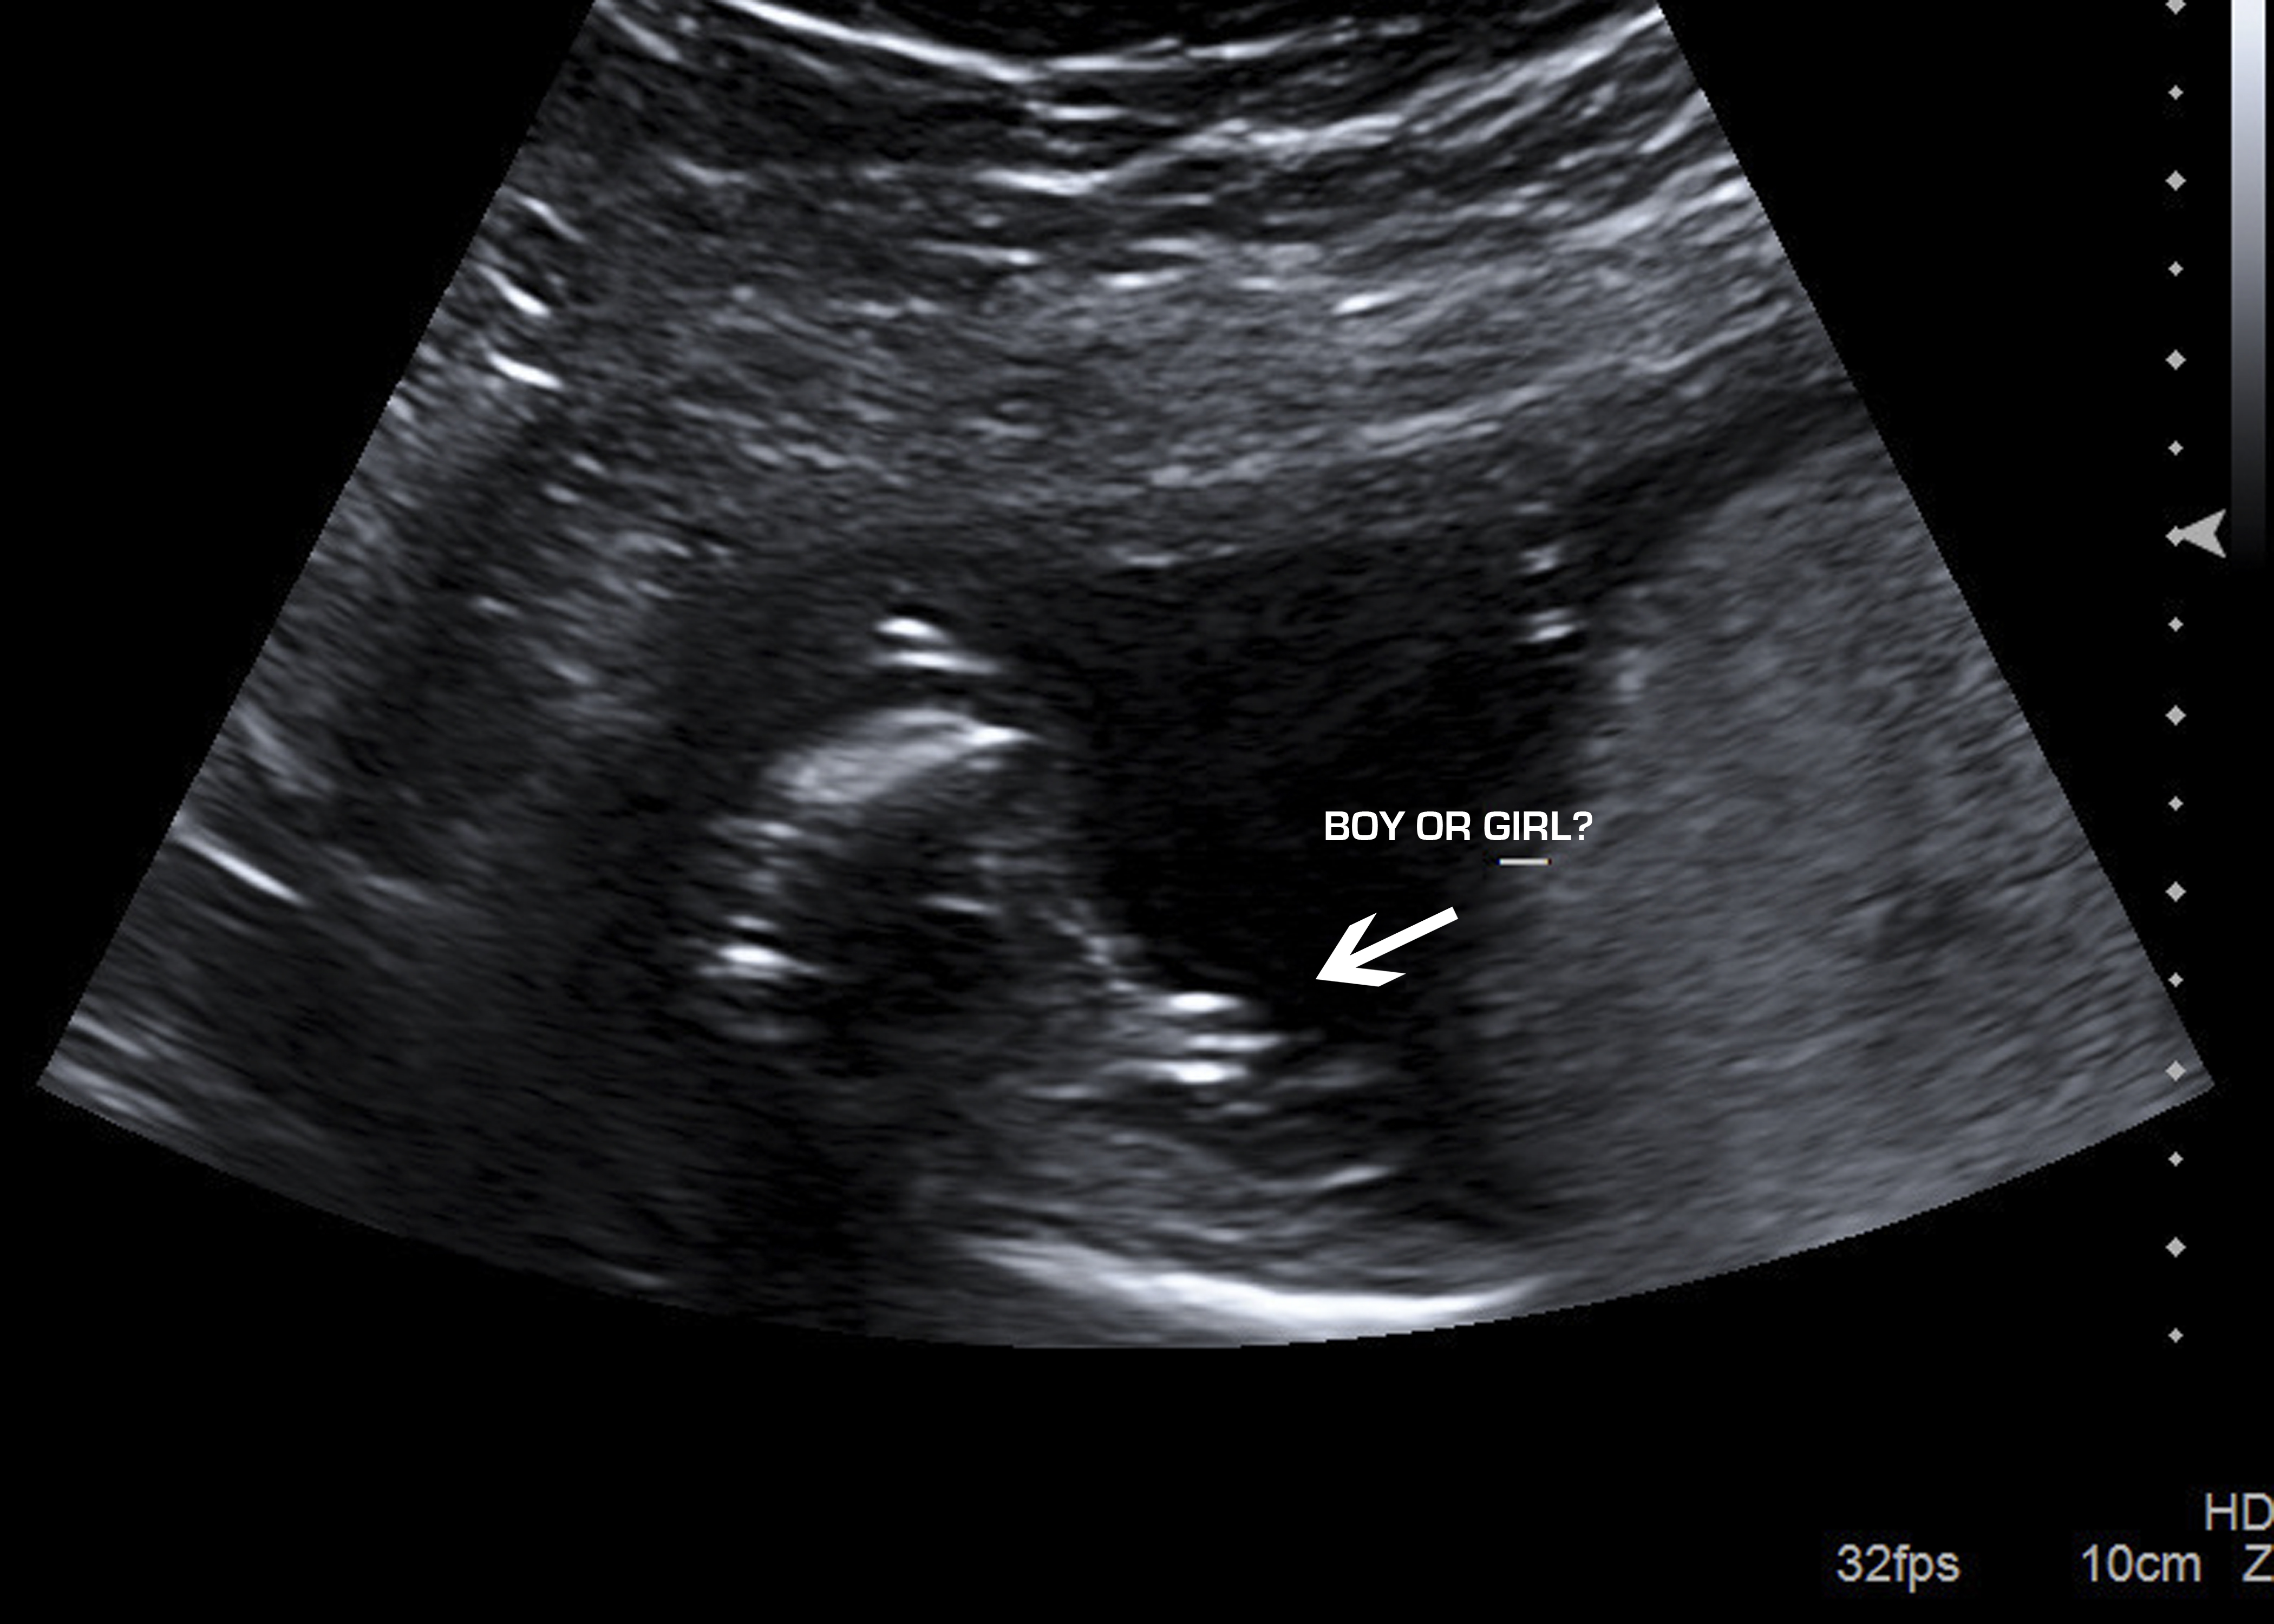

They say if it looks like a hamburger, it's a girl. a turtle, it's a boy.  That looks like a hamburger... so girl!  So what did the tech say??

• May first I thought girl because of the three lines but it also sticks out a little far in the middle, so I don't know!!

• I want to say girl because the 3 lines, but a girls parts and not stuck out like that. So makes me think boy. Could be because the baby was active like you said...

May first I thought girl because of the three lines but it also sticks out a little far in the middle, so I don't know!!

• I work at a 3d/4d ultrasound facility. Sometimes the umbilical cord can be inbetween the legs and the three vessels look like three lines for a girl.